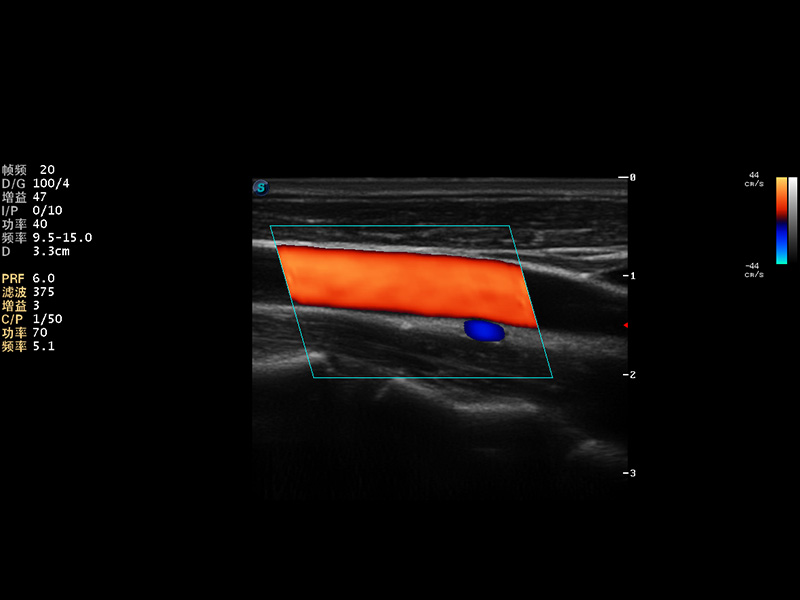

S9便携式彩色多普勒超声诊断仪是玖鼎集团研发的高端便携彩超设备,外观设计新颖、产品性能卓越。S9在便携超声领域采用了突破传统的触摸屏交互设计,并以先进的软件硬件技术和设计理念,为您带来清晰的图像质量、稳定的工作性能和便捷的操作体验。

AutoC智能血流追踪